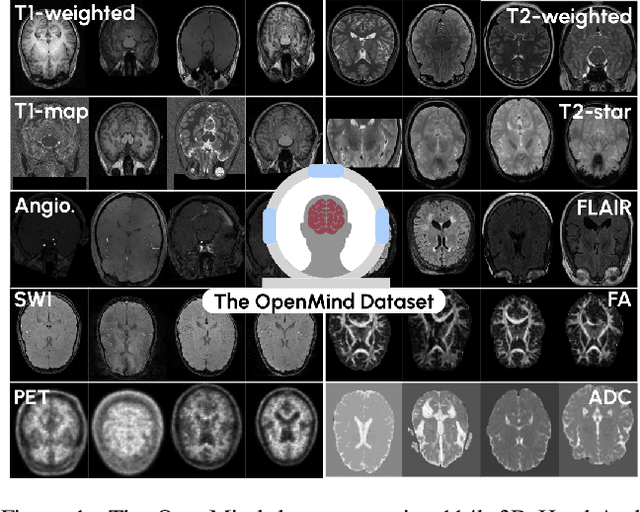

Abstract:The field of 3D medical vision self-supervised learning lacks consistency and standardization. While many methods have been developed it is impossible to identify the current state-of-the-art, due to i) varying and small pre-training datasets, ii) varying architectures, and iii) being evaluated on differing downstream datasets. In this paper we bring clarity to this field and lay the foundation for further method advancements: We a) publish the largest publicly available pre-training dataset comprising 114k 3D brain MRI volumes and b) benchmark existing SSL methods under common architectures and c) provide the code of our framework publicly to facilitate rapid adoption and reproduction. This pre-print \textit{only describes} the dataset contribution (a); Data, benchmark, and codebase will be made available shortly.